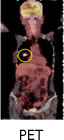

PET(Positron Emission Tomography・ペット)

がんに特異性の高い検査方法です。がん細胞は、正常細胞に比べて活動性が高く、たくさんのブドウ糖を必要とします。この性質を利用して、ブドウ糖が多く集まる場所を発見することでがんを早期発見できる検査です。アイソトープをくっつけたブドウ糖を静脈注射するとがんやがんの転移巣に陽性反応が現れます。思わぬところのがんが見つかったりする事もありますが、小さながんや初期のがんは見つからないこともあります。また、がん以外の病気でも陽性反応が出ることがありますので専門医による正確な診断が必要です。